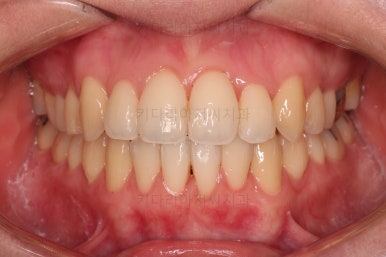

초진 시, 입안의 모습입니다.

좌측 송곳니가 덧니처럼 튀어나가 있고, 송곳니 옆의 작은 억므니가 안으로 쏙 들어가서 덧니 느낌이 더 강조되어 보이네요.

위아래 앞니가 긴밀하게 겹침이 없는 약간의 개방교합(오픈바이트, Openbite) 경향이 보입니다.

웃거나 말할 때 드러나는 치열이 삐뚤어서 심미적으로 좋지 못하고요.